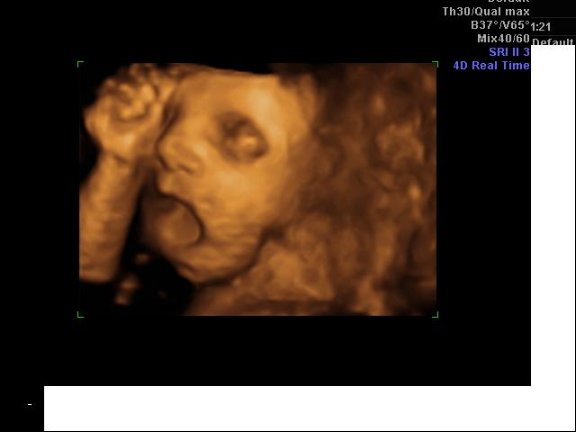

Egy bizonyíték a kukira: Kép

Nagyon szép lett Milán szobája! Ügyes vagy! A kissrác büszke lesz az anyukájára! :) A 4D-s képek! :):):) Szuperek! Milánnak olyan szép kis arcocskája van, hogy csak csuda! :) Nagyon szép! :)